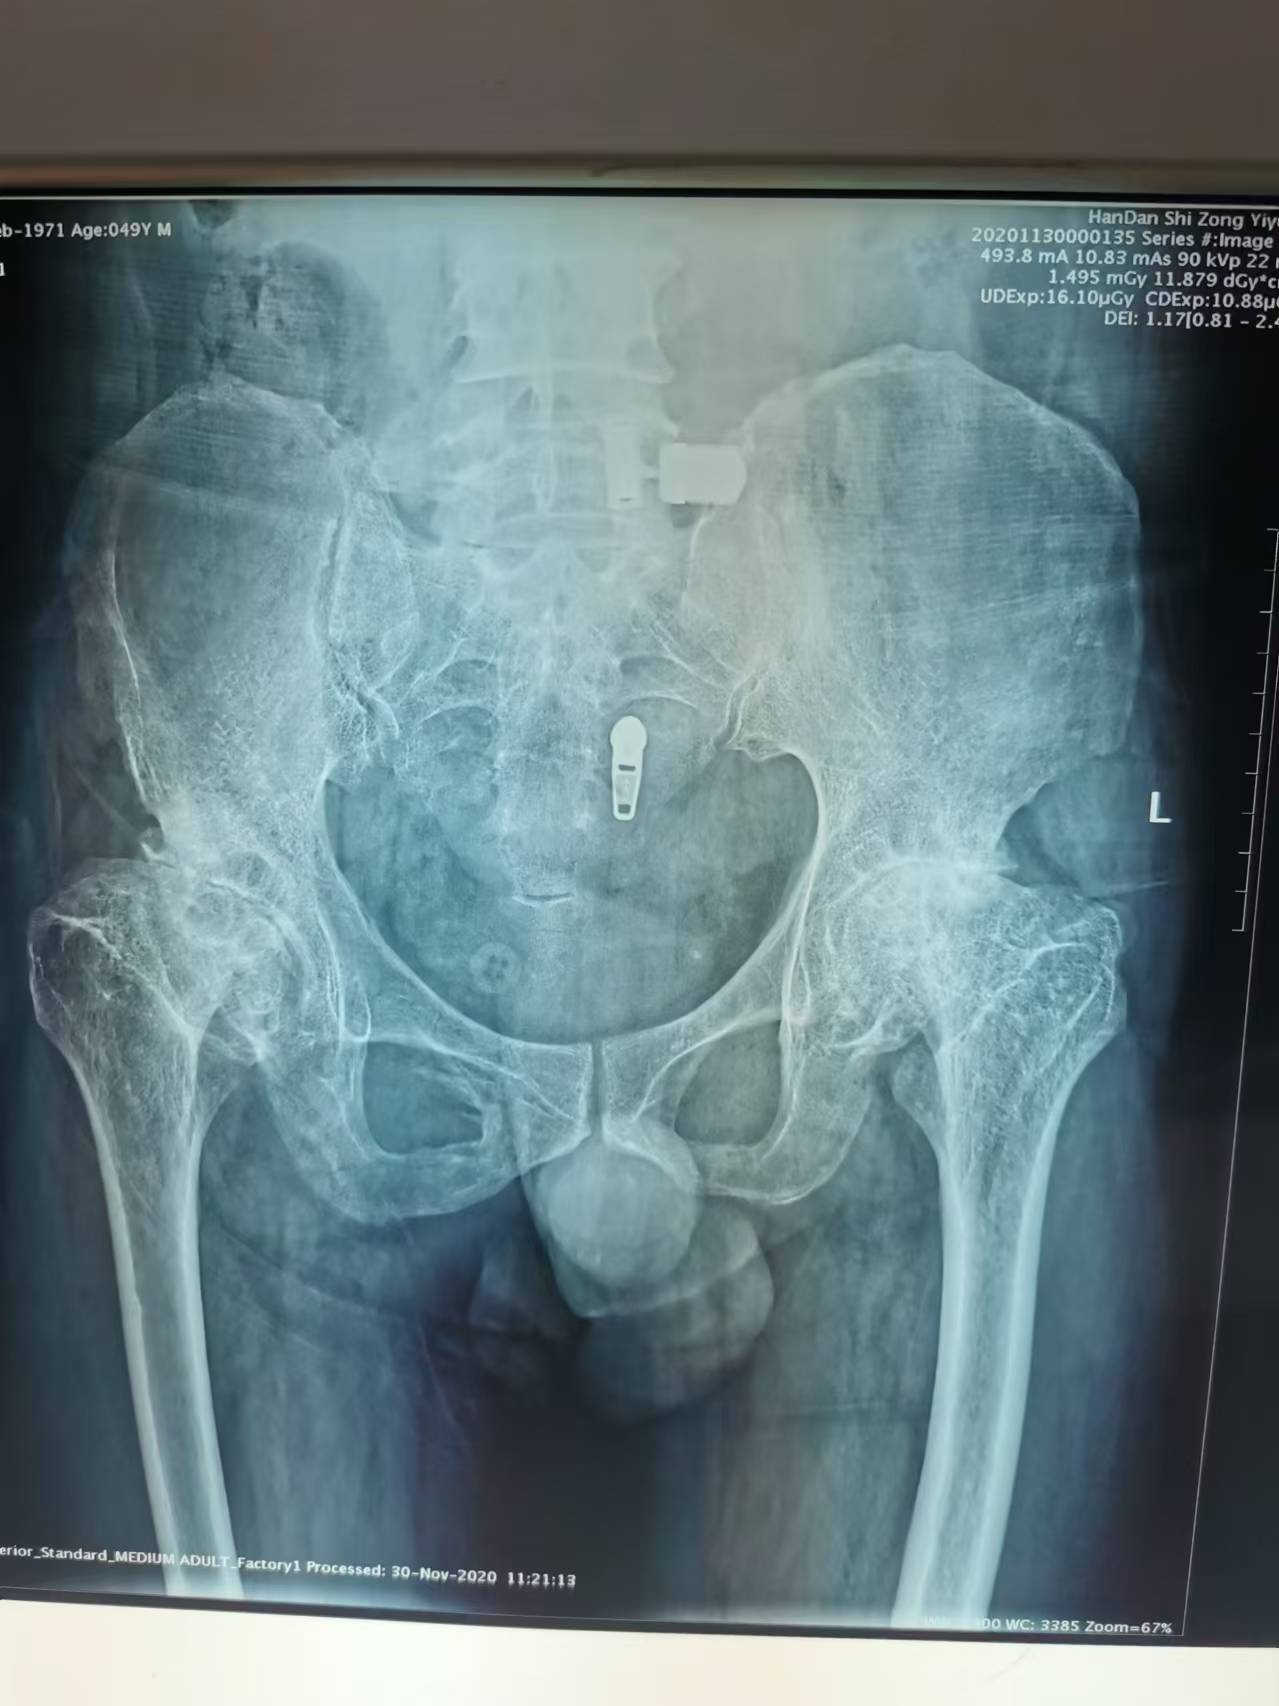

首页 > 张恒云工作室 > 影像资料 二